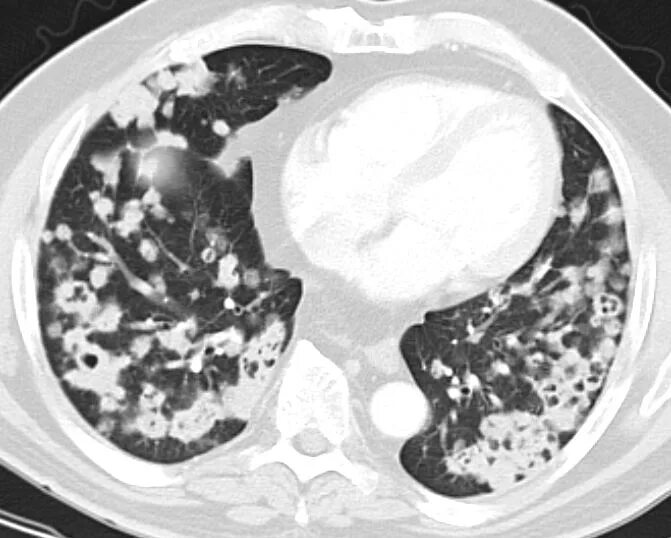

Метастазы в матке